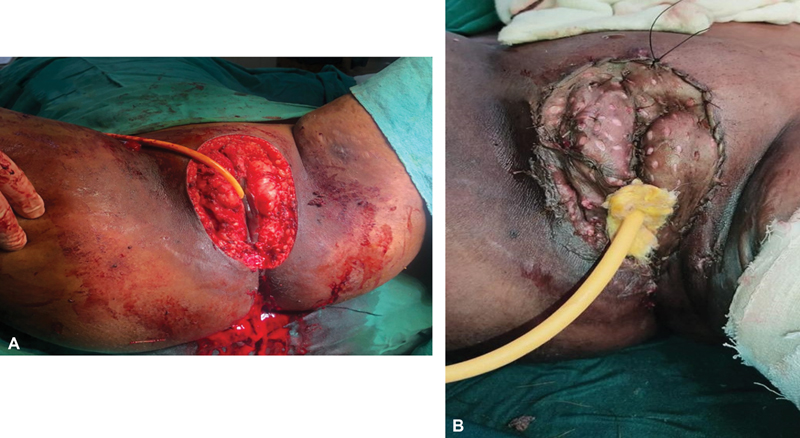

Simple vulvectomy with split skin graft reconstruction was planned after consultation with plastic surgeons. Simple vulvectomy was done ([Fig. 2A]). Vulval reconstruction was performed by harvesting grafts of intermediate thickness from the left thigh and placing them over the excision site ([Fig. 2B]). The plane of dissection was along the line of cleavage. Gross examination of the excised specimen showed a vulval excised flap of 13*9*4 cm with the skin surface showing wart-like growth. The satellite lesions on the thighs, perianal region, and labia minora were separately excised. Postoperative period was uneventful. The diagnosis of condyloma acuminatum with a moderate degree of dysplasia was confirmed by the final histopathology report ([Fig. 3]). Immunohistochemically, it was CD ⅚ positive, p63 positive, and p16 negative. Her functional outcome was good and was disease free even after 13 months postsurgery.

Fig 2 : (A, B) Intraoperative picture. (A) Simple vulvectomy. (B) Split skin grafting done over the defect.

Fig 2 : (A, B) Intraoperative picture. (A) Simple vulvectomy. (B) Split skin grafting done over the defect.